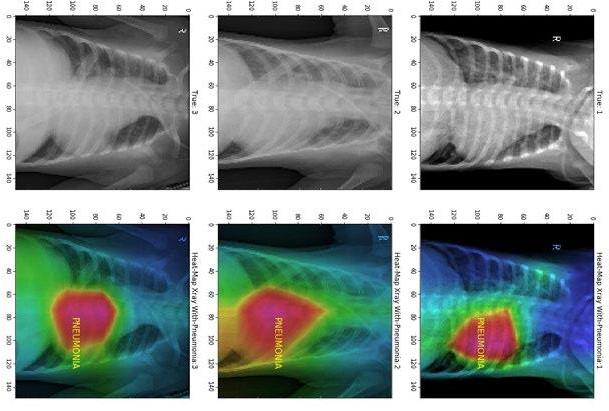

Figure 1

Healthcare companies are also now looking for effective point-of-care solutions to provide cost-effective and faster diagnosis and treatment in the field or in locations away from large hospitals. As a result, there’s rising demand to perform accurate image inferences to efficiently detect respiratory diseases like pneumonia in the field and provide clinical care using small, portable and point-ofcare devices at the edge. Spline.ai (a partner of Xilinx) has developed a model using curated, labeled images for X-ray classification and disease detection (Figure 1). The model - trained using datasets from the National Institute of Health (NIH), Kaggle and from the likes of Stanford and MIT - can detect pneumonia with greater than 94% accuracy today. The model is then deployed and optimized on Xilinx’s